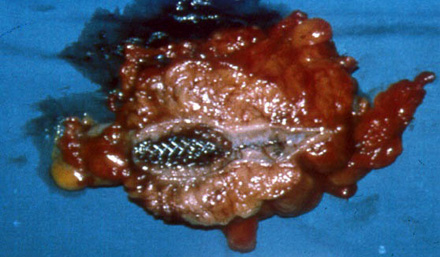

Photograph of resected segment of colon with stent in- situ.

Stenting

The principles behind stenting are:

- Place a stent through the stenotic area by radiologist/endoscopist

- Deflate proximal bowel

- Turn emergency into elective situation